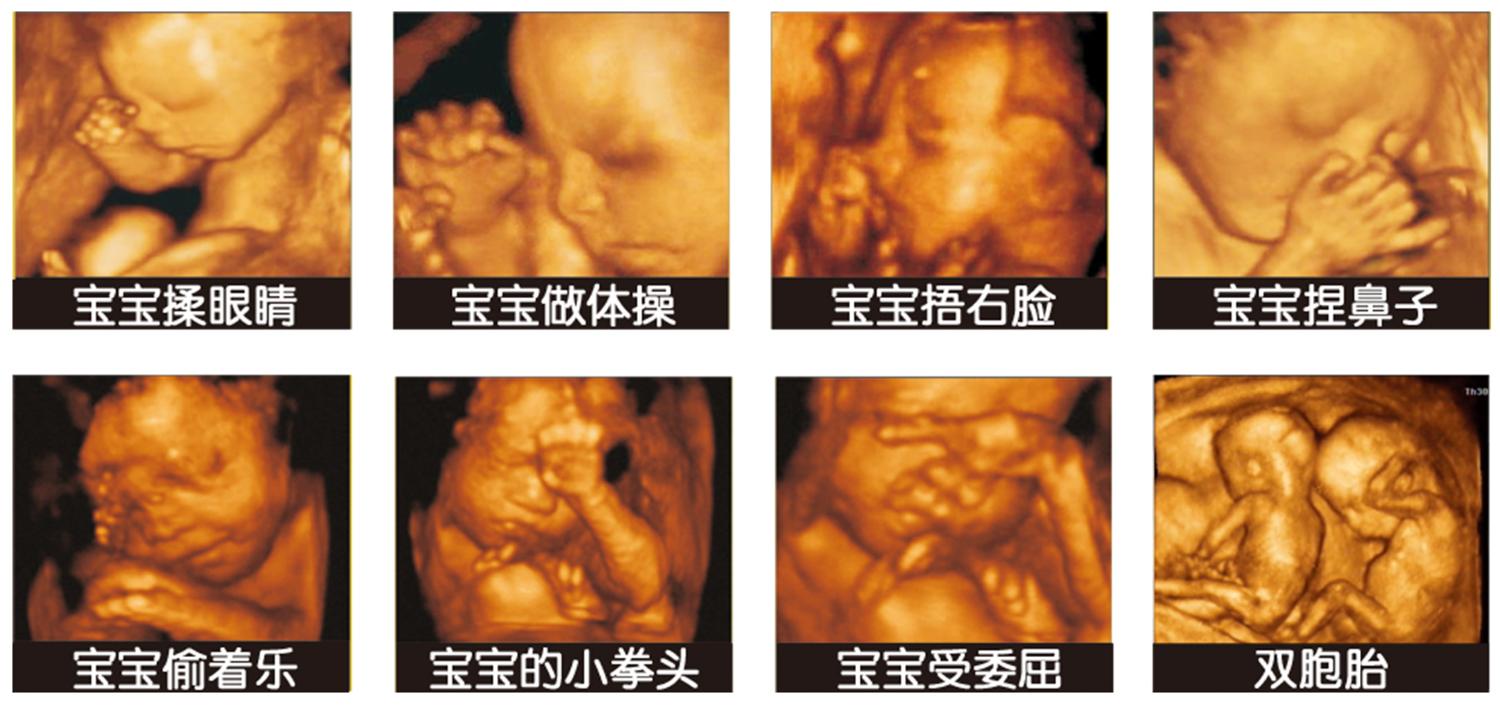

四维彩超是目前最为先进的彩色超声设备,简单点说就是把原有的二维彩超的图片通过软件加工成立体图像,这样能够提高诊断的准确率。

其实以实际情况来看,很多准妈妈之所以愿意做四维彩照,最主要还是想看看胎儿的模样,看看胎儿在子宫里是如何活动的,因此也有一些人会将四维彩超称之为“子宫内写真集”。

为什么胎儿的四维照会那么丑

1. 胎儿还没有发育完全

这个时候宝宝还在发育的阶段,根本没有发育完全,而且此时的胎儿浑身都的胎脂,这样四维彩超拍出来的时候,也只能排到大概轮廓。

2. 拍摄的角度不好

我们拍照片的时候还需要摆个姿势才会好看,胎儿在妈妈肚子里只能保持卷曲的状态,而一般拍摄四维彩照的时候,医生主要还是为了排畸,也就会容易忽略拍摄角度的问题。

3. 四维彩超不是高清照相机

四维彩超只是一个大概影像,它不可能像照相机一样拍摄的特别清晰,也不能捕捉到胎儿的各种细节部位,而且在最后医生还会对个部位进行放大,这样就会出现胎儿大嘴巴大鼻子的情况。

其实对于四维彩超的呈现出来的画面,准妈妈不要太在意,很多胎儿在出生后跟四维照里的模样根本不一样,而且宝宝刚生出来需要几个月之后才能变好看,所以准妈妈不要着急。